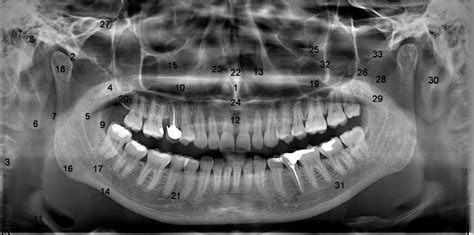

Alright, guys, let’s dive into the fascinating world of radiographic visibility! Have you ever wondered why some anatomic structures pop on an X-ray while others seem to hide? It’s all about understanding the principles that govern how radiographic images are formed. When we talk about visibility, we’re essentially referring to the ability to distinguish between different tissues and structures on a radiograph. This clarity hinges on several key factors, including radiographic density, contrast, and the absence of artifacts. Achieving optimal visibility is crucial for accurate diagnosis and effective treatment planning. So, whether you’re a seasoned radiologist or just starting out, mastering the art of radiographic visibility is essential. Stick with me, and we’ll explore the ins and outs of this critical aspect of medical imaging!

First up, we have radiographic density. This refers to the degree of blackness on a radiograph. The denser the structure, the more X-rays it absorbs, resulting in a lighter (or more radiopaque) appearance on the image. Conversely, less dense structures allow more X-rays to pass through, leading to a darker (or more radiolucent) appearance. Bone, for example, is quite dense due to its high calcium content, making it appear bright on a radiograph. Air, on the other hand, is much less dense, resulting in darker areas. Understanding radiographic density is fundamental to interpreting radiographs accurately. Variations in density can indicate the presence of abnormalities, such as tumors or fractures. Factors affecting density include the thickness of the tissue, its composition, and the energy of the X-ray beam. In clinical practice, adjusting technical factors like kVp and mAs allows us to optimize radiographic density for different body parts and diagnostic purposes.

Next, let’s talk about contrast. Radiographic contrast is the difference in density between adjacent structures on a radiograph. High contrast means there’s a significant difference in density, making it easier to distinguish between structures. Low contrast, on the other hand, makes it difficult to differentiate between tissues. Contrast is influenced by factors such as the energy of the X-ray beam (kVp), the type of tissue being imaged, and the use of contrast agents. For instance, imaging soft tissues often requires the use of contrast agents to enhance visibility. These agents, like barium or iodine, increase the density of specific structures, making them more visible. Proper contrast is essential for detecting subtle abnormalities and ensuring accurate diagnoses. Radiologists carefully adjust technical factors and contrast agents to achieve the optimal level of contrast for each specific examination.